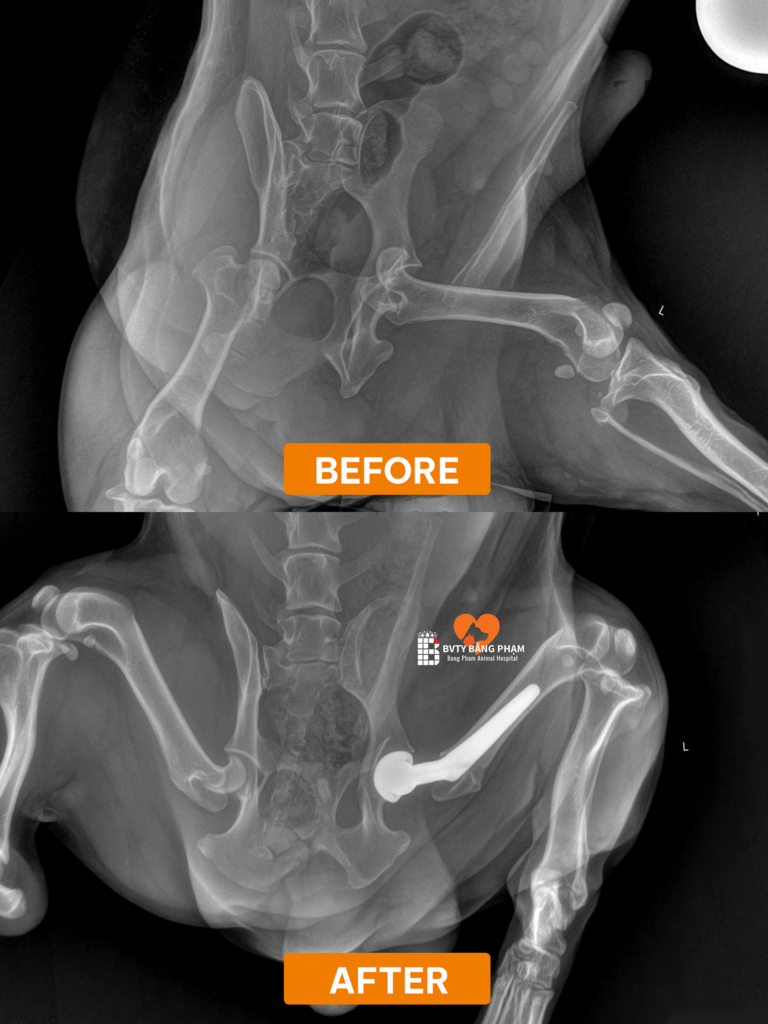

Qua quá trình thăm khám lâm sàng và chụp X-quang, các bác sĩ tại Bằng Phạm đã chẩn đoán chính xác: Bum bị đứt dây chằng khớp háng hoàn toàn.

Về mặt giải phẫu, dây chằng khớp háng đóng vai trò như một “dây neo” vô cùng quan trọng, giúp giữ chặt chỏm xương đùi nằm yên vị trong ổ cối xương chậu. khi chó bị đứt dây chằng khớp háng, toàn bộ cấu trúc khớp háng sẽ trở nên lỏng lẻo, dẫn đến tình trạng trật khớp, tê liệt vận động và gây ra những cơn đau dữ dội. Đứng trước chấn thương nghiêm trọng này, việc can thiệp ngoại khoa là con đường duy nhất để giải cứu Bum.

Sau khi hội chẩn, các bác sĩ chỉ định thực hiện Phẫu thuật Thay khớp háng toàn phần (Total Hip Replacement – THR). Đây được xem là “tiêu chuẩn vàng” trong việc điều trị các chấn thương khớp háng nặng nề với 3 mục tiêu cốt lõi: loại bỏ hoàn toàn cơn đau, tái tạo cấu trúc giải phẫu ổn định và phục hồi chức năng vận động tối đa.

Ca đại phẫu được thực hiện với sự hỗ trợ của bộ dụng cụ chuyên dụng BlueSAO. Quy trình đòi hỏi sự chính xác tuyệt đối, bao gồm các bước:

• Tiếp cận vùng khớp háng, tiến hành cắt bỏ toàn bộ các phần xương và sụn đã bị tổn thương.

• Lắp đặt một ổ cối nhân tạo để thay thế cho phần ổ cối tự nhiên.

• Thay thế chỏm xương đùi cũ bằng một chỏm kim loại cao cấp, có chân cắm vững chắc vào trong lòng xương đùi.

• Cuối cùng, lắp ghép hai bộ phận nhân tạo này lại với nhau để tạo thành một khớp háng mới, đảm bảo độ vững chãi và biên độ vận động linh hoạt.